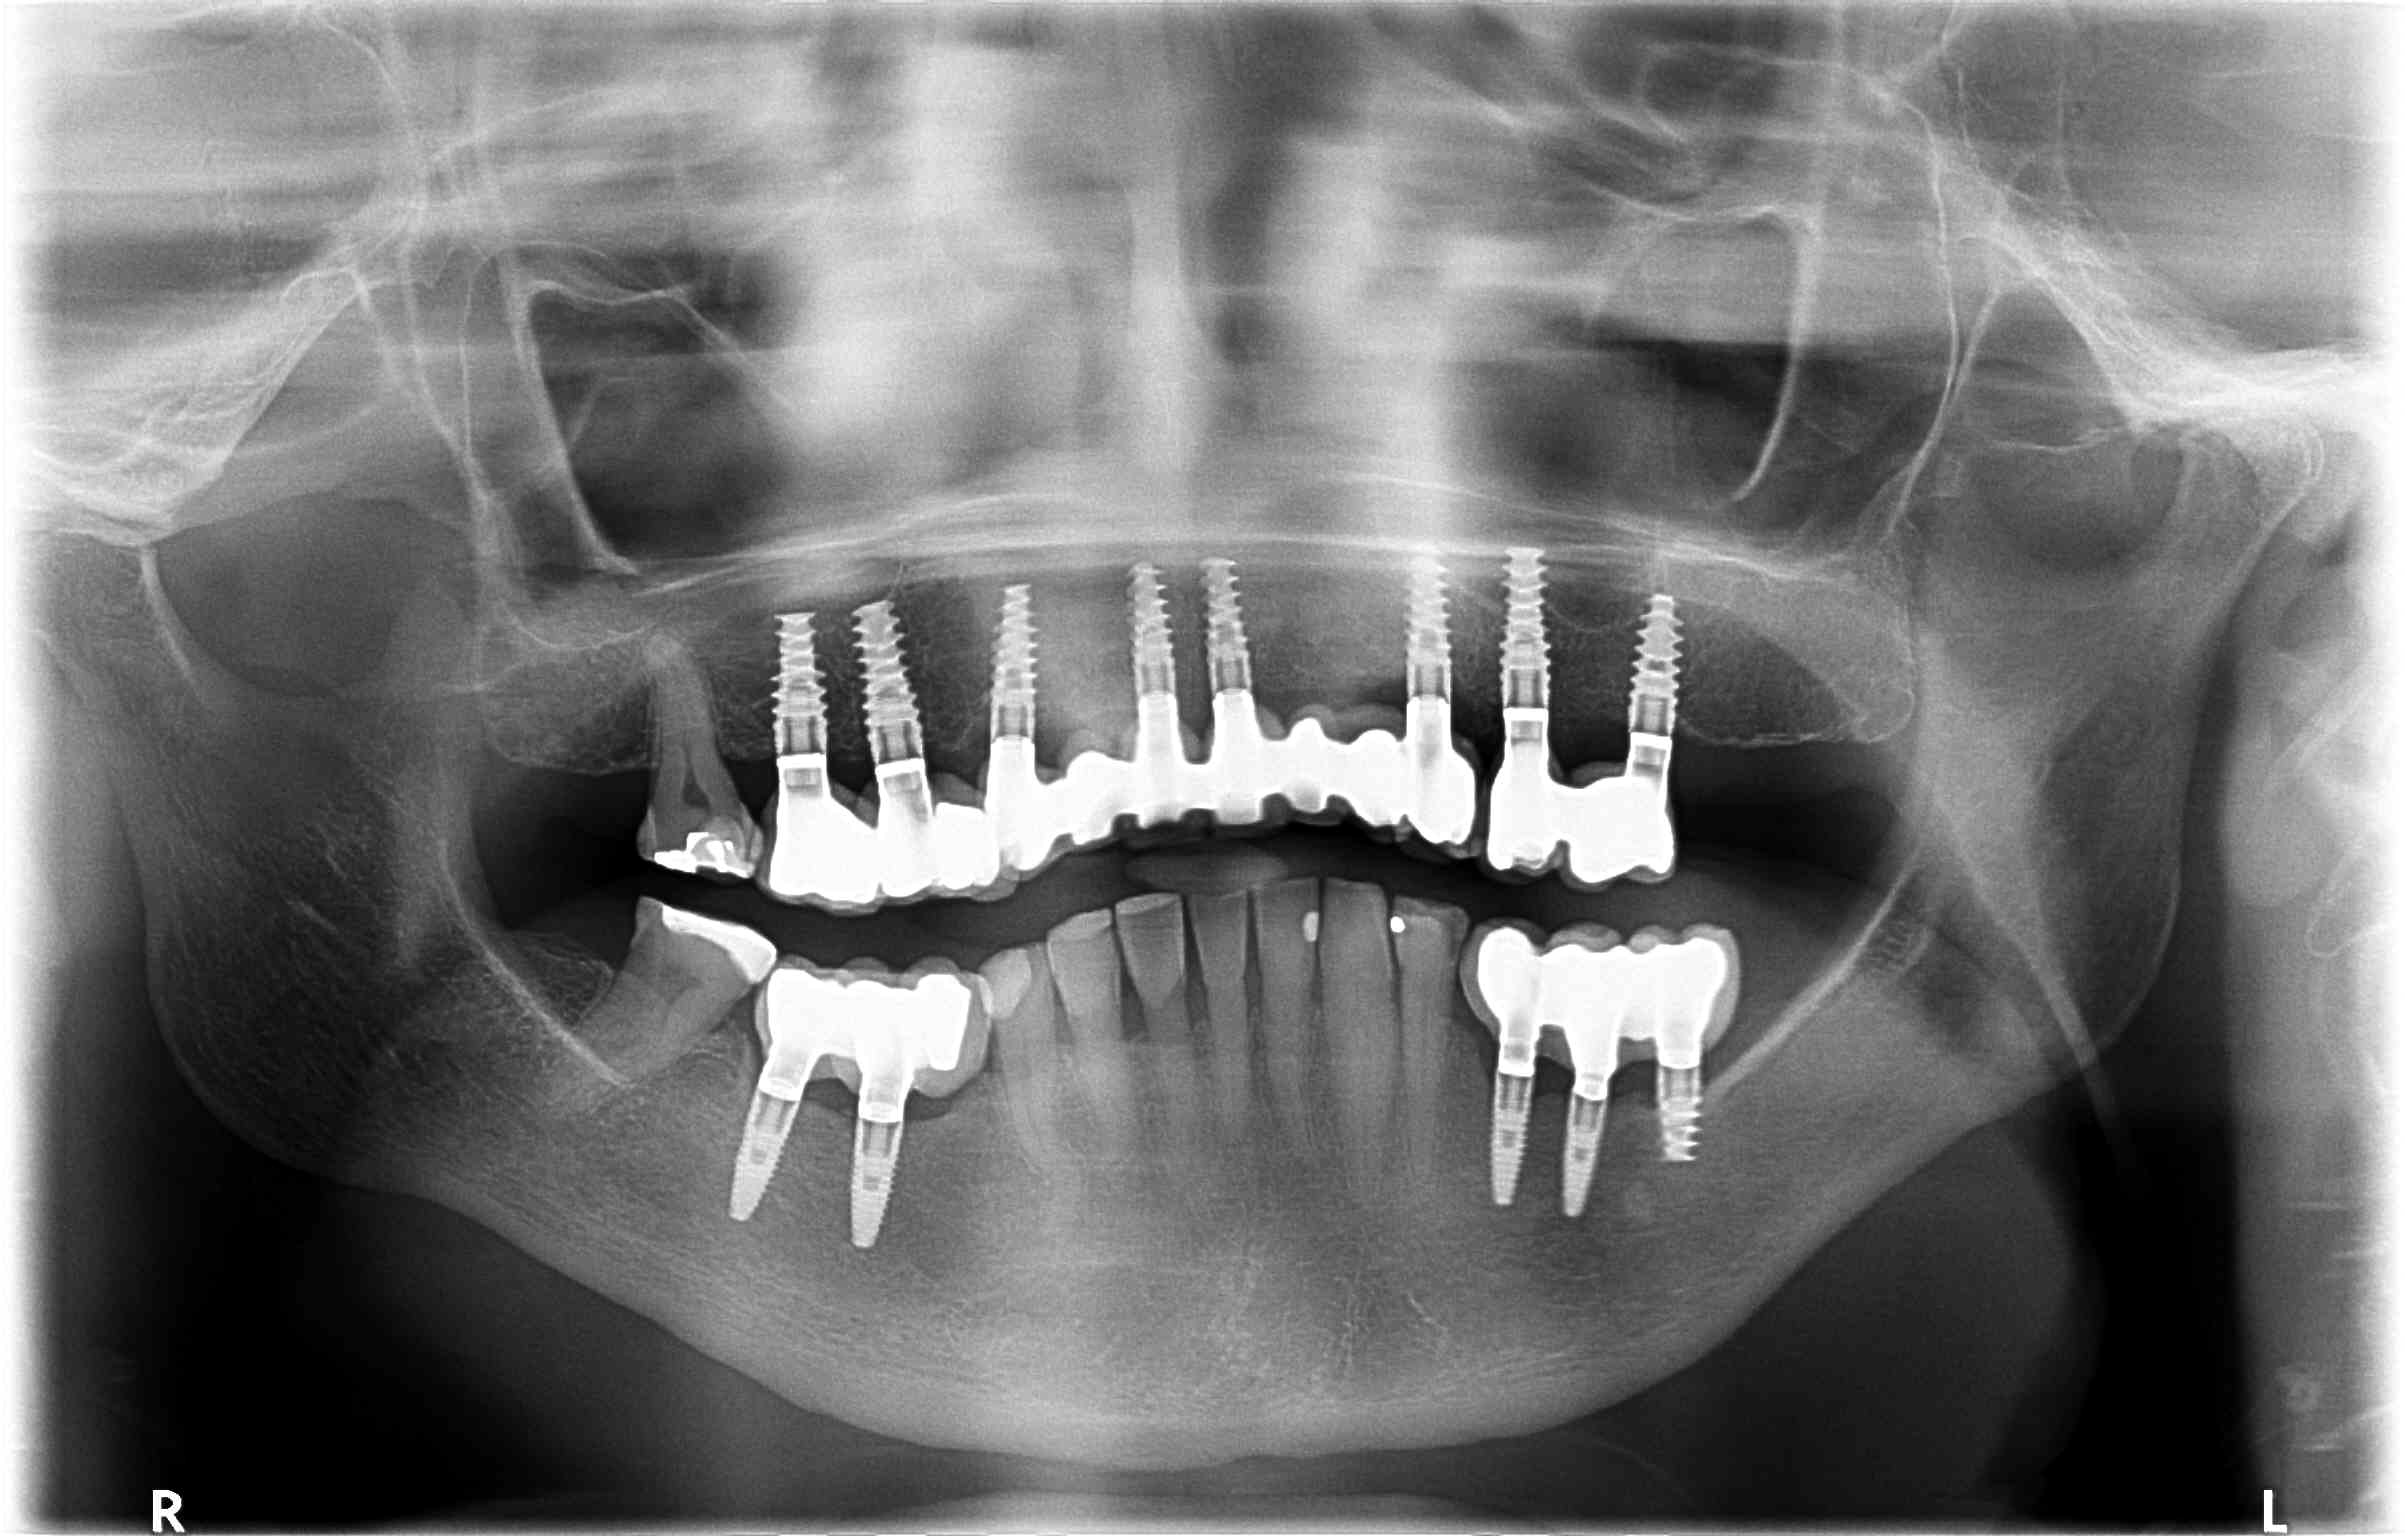

8 implantes superiores

Implantología avanzada